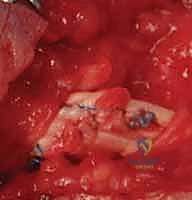

2. الشق الجراحي (Incision)

لا يتم قطع الجلد بشكل مستقيم أبداً لتجنب الانكماش الندبي. يستخدم الجراح شقوقاً متعرجة مثل شق برونر (Bruner Zig-Zag Incision) أو الشق الجانبي الأوسط (Mid-lateral). هذا يسمح بكشف واسع للأوتار مع حماية الأعصاب والأوعية الدموية.

3. استكشاف الأوتار وتحديد الأطراف (Retrieval)

هذه هي المرحلة الأكثر دقة. يجب العثور على طرفي الوتر المقطوع. في المنطقة الثانية، قد ينسحب الطرف القريب إلى راحة اليد. يستخدم الجراح أدوات مجهرية دقيقة وقثاطير مرنة لسحب الوتر بلطف دون إتلاف سطحه الأملس، وتمريره مرة أخرى عبر نظام البكرات (Pulleys).

4. تقنيات الخياطة الجراحية (Suturing Techniques)

الهدف هو تحقيق خياطة قوية بما يكفي لتحمل الحركة المبكرة، وفي نفس الوقت ملساء بما يكفي لتنزلق داخل الغمد الضيق.

* الخياطة الأساسية (Core Suture): يتم استخدام خيوط قوية غير قابلة للامتصاص. يعتمد د. هطيف على تقنيات حديثة متعددة الخيوط (4-strand أو 6-strand repair) مثل تقنية (Strickland) أو (Modified Kessler). كلما زاد عدد الخيوط العابرة للوتر، زادت القوة، ولكن زاد حجم العقدة، لذا فالتوازن مطلوب.

* الخياطة المحيطية (Epitendinous Suture): بعد الخياطة الأساسية، يتم استخدام خيط رفيع جداً (مثل 6-0) لخياطة الحواف الخارجية للوتر بغرز مستمرة. هذه الخطوة تزيد من قوة الإصلاح بنسبة تصل إلى 30% وتجعل سطح الوتر أملساً جداً لتقليل الاحتكاك والالتصاقات.

5. التعامل مع الغمد والبكرات (Pulley Management)

يحرص د. هطيف أشد الحرص على الحفاظ على بكرات A2 و A4. إذا تم قطعها أثناء الإصابة، يتم ترميمها لضمان عدم حدوث تقوس للوتر (Bowstringing) مستقبلاً.

6. إصلاح الأعصاب والأوعية الدموية

نظراً لأن الأعصاب الرقمية تسير بمحاذاة الأوتار، يتم فحصها بدقة تحت الميكروسكوب الجراحي. إذا كانت مقطوعة، يتم خياطتها باستخدام خيوط مجهرية دقيقة جداً (9-0 أو 10-0) لاستعادة الإحساس للإصبع.